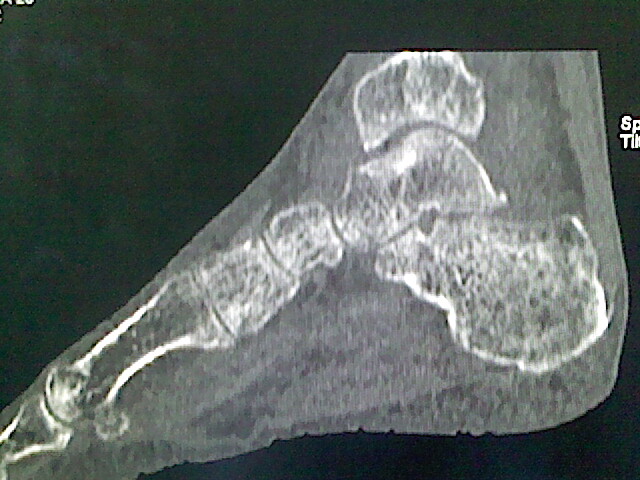

男,76岁,左小腿疼痛,不能站立

本例骨质改变主要表现为滑膜或韧带区的骨侵蚀融解(胫腓联合区骨质破坏无硬化边),距骨后部骨质破坏区有硬化边及死骨样改变.所以,本例考虑关节结核可能性大,绒毛膜结节性滑膜炎多发于中年,且极少见于膝髋以外的关节,骨质硬坏也以压陷吸收为主,有明显的硬化边,骨膜增生呈结节状(可以mr鉴别),所以本例暂除外.

另不除外可引起相似表现的其他炎症如布氏杆菌性关节炎等